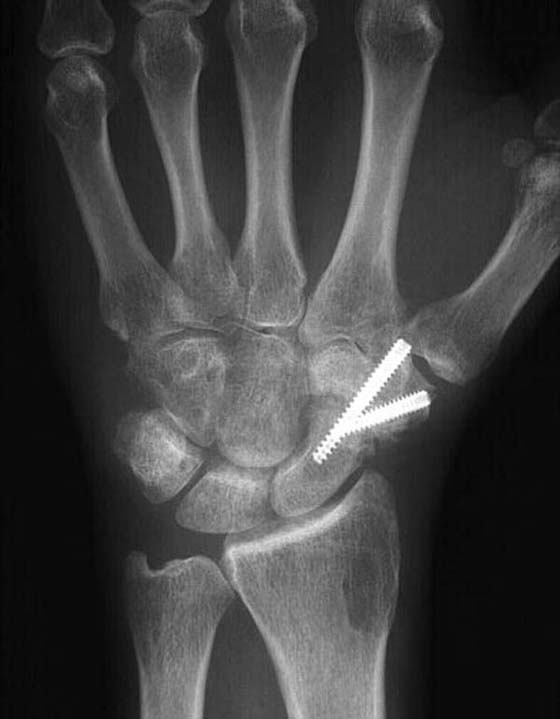

Scaphotrapezial Trapezoidal Arthrodesis

Fusion of the scaphotrapezial trapezoidal (STT) joint is indicated in the treatment of degenerative arthritis of the STT joint (Fig. 76-1). STT fusion offers good pain relief in patients with STT arthrosis.7 It maintains grip and pinch strength without sacrificing functional motion. STT arthrodesis is also indicated in the treatment of AVN of the lunate.8 The STT fusion has been shown to be effective in unloading the lunate at the expense of increased radioscaphoid contact. This load transfer may eventually lead to degenerative arthritis of the radioscaphoid joint.9,10 STT fusion has also been advocated for scapholunate instability.11 Long-term studies have demonstrated significant problems with the procedure, with a 50% complication rate.12 For this reason, it is important that postoperative therapy include education regarding long-term joint protection techniques.

The surgical technique involves fusion of the distal pole of the scaphoid to the trapezium and trapezoid via a dorsal approach. Internal fixation is used to maintain the scaphoid in an extended position to maintain proper carpal alignment (Fig. 76-2). Distal radial bone grafting is used. The procedure prevents scaphoid flexion and extension and will alter carpal motion.

images

Figure 76-2 Scaphotrapezial trapezoidal arthrodesis.